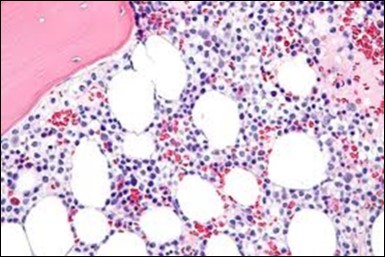

The classic hairy cell is medium sized with a magnitude of 10-14µm. The moderately abundant or variable cytoplasm may be transparent or mildly basophilic. The cellular surface with the characteristic serrated perimeter depicts innumerable fragile or stout extensions of cytoplasm ,particularly discernible on the phase contrast and electron microscopy. The cytoplasm may exhibit vacuoles with occasional azurophilic granules4. The nucleus may be elliptical or reniform, folded or indented with a coarse, reticulated or a finely dispersed chromatin and inconspicuous nucleoli along with infrequent mitosis. Bone marrow aspiration or bone marrow trephine biopsy may be inadequate for diagnosis in 30%-50% individuals4. The trephine sections of the bone marrow may depict a characteristic interstitial pattern of leukaemic infiltration. Generally the bone marrow is hyper-cellular, though it may be hypo-cellular in 10-15% individuals4. The leukaemia cell ingress may be diffuse or partial, although diffuse infiltration is frequent. The partial variety of leukaemic dissemination may be ineptly categorized with an indeterminate differentiation from the uninvolved marrow. The malignant insertions may initially emerge as miniature, undefined, cellular loci. The formalin fixed, paraffin embedded sections may elucidate a crystalline zone or a “halo” appearance of the cells with a circumscribed nucleus on account of the plentiful cytoplasm4. The cellular margins may be intertwined. Fixation of bone marrow smears with Zenker’s fixative may demonstrate a retracted cytoplasm of the hairy cells with a consequent disconnected structure. The bone marrow in the absence of a malignant process may be hypo-cellular or hyper-cellular. Reticulin stains may delineate an enhanced accrual of broad, dense reticulum fibres surrounding the aggregates of leukaemia cells with the fibrous circumlocution of individual malignant cell and fibrotic extensions into the abutting, uninvolved bone marrow4.

The leukaemia cells may enunciate a characteristic immune phenotype, crucial for a confirmatory diagnosis. The peripheral blood mononuclear B cell population may display a kappa or lambda light chain restriction. The phenotype of classic hairy cell leukaemia may be delineated by concurrent, immune reactive CD19+ CD20+,CD 11c+, CD25+, CD103+ and CD123+. An intensely immune reactive CD200+ and a non reactive CD27- antigen may be present2, 4. Evaluation of a trephine bone marrow biopsy and bone marrow aspirate may define the degree of tumour infiltration. A dry tap on account of prominent bone marrow fibrosis may be elucidated at preliminary diagnosis. A decline in the normal haematopoiesis may account for a hypo-cellular marrow in 10% instances. Gradation of cellular infiltrating of the leukaemia within the bone marrow may be appropriately investigated with immune –histochemical stains2, 4. Immune staining for CD20+, annexin 1 and VE1 (a BRAF V600E stain] may validate the diagnosis and precisely analyse the extent of malignant bone marrow infiltration[8]. Determination of BRAF V600E mutation may be critical in therapeutically non responsive individuals with applicable standard therapy or in instances of multitudinous reoccurrences[9]. Deploying inhibitors of BRAF V600E gene may be efficacious in patients impervious to approved therapy. The mutation necessitates a comprehensive scrutiny of the implicated individuals with a sensitive molecular assay which may discern up to < 10% of the hairy leukaemia cells appearing in the peripheral blood smears or bone marrow aspirates diluted with peripheral blood or aspirates elucidating a dry tap[2,4]. Allele specific polymerase chain reaction (PCR) or a next generation sequencing may be optimally employed to circumvent false negative outcomes. If the leukaemia cells are sparse or if particularly sensitive & efficacious molecular techniques are not accessible, the application of appropriate immune histochemical stains to the bone marrow biopsy such as a BRAF V600E mutation stain (VE1) may detect the hairy cells and conclusively diagnose the condition[2,4,10]. Figure 1, Figure 2, Figure 3, Figure 4, Figure 5, Figure 6, Figure 7, Figure 8, Figure 9, Figure 10, Figure 11, Figure 12, Figure 13, Figure 14.

Figure 7.HCL: blebs on the cellular surface with fine nuclear chromatin(23).

Figure 8.HCL: widely disseminated hairy cells within the bone marrow trabaculae(24).

Figure 9.HCL: hairy cells within a bone marrow trephine biopsy(25).